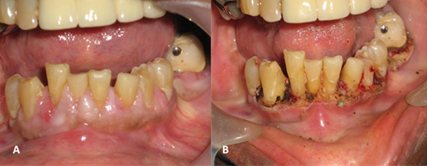

Caso clínico 1

Paciente de sexo masculino de 60 años de edad, acudió a la consulta por presentar incomodidad de las encías en el sector inferior (Figura 1). Refirió tener antecedentes de hipertensión arterial hace 15 años, en manejo crónico con amlodipino 10mg/día desde el momento de inicio de tratamiento. Al realizar examen clínico se observó aumento el volumen de la encía marginal y papilar, de aspecto lobulado, y de color rosa pálido, excepto en encía papilar distal de OD#42. Asimismo, se observó hiperpigmentación melánica en encía adherida del maxilar inferior (Figura 1A). El procedimiento quirúrgico se realizó bajo anestesia local mediante incisión a bisel externo con electrobisturí, el paciente presentó ligero sangrado sin complicaciones (Figura 1B).